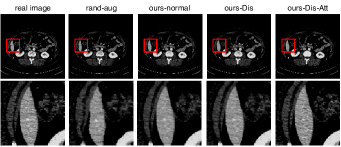

Synthetic images of some methods in SLIVER07 and CHAOS2019 are shown in Figure 2 and Figure 3. Considering that , and do not change the texture of the images, we show only the real image and the synthetic images of , , and . From Figure 2 and Figure 3, we can see that the edge of the synthetic image using elastic transformations (column 2) is not smooth. One possible reason is that elastic transformation makes random movement on the original image to generate the new image, which will make some sharp angle in the edge of the synthetic image. By contrast, our method (column 3 to 5) can generate the image with a more smooth edge, which means the synthetic image is more realistic than the image generated by elastic transformations. In Figure 2 and Figure 3, (column 5) has the more clear texture in the object than (column 3) and (column 4), which means the synthetic image is more realistic than the image generated by (column 3) and (column 4) in the target object. This result demonstrates that the two discriminators with the attention mechanism can improve the authenticity of the synthetic image.